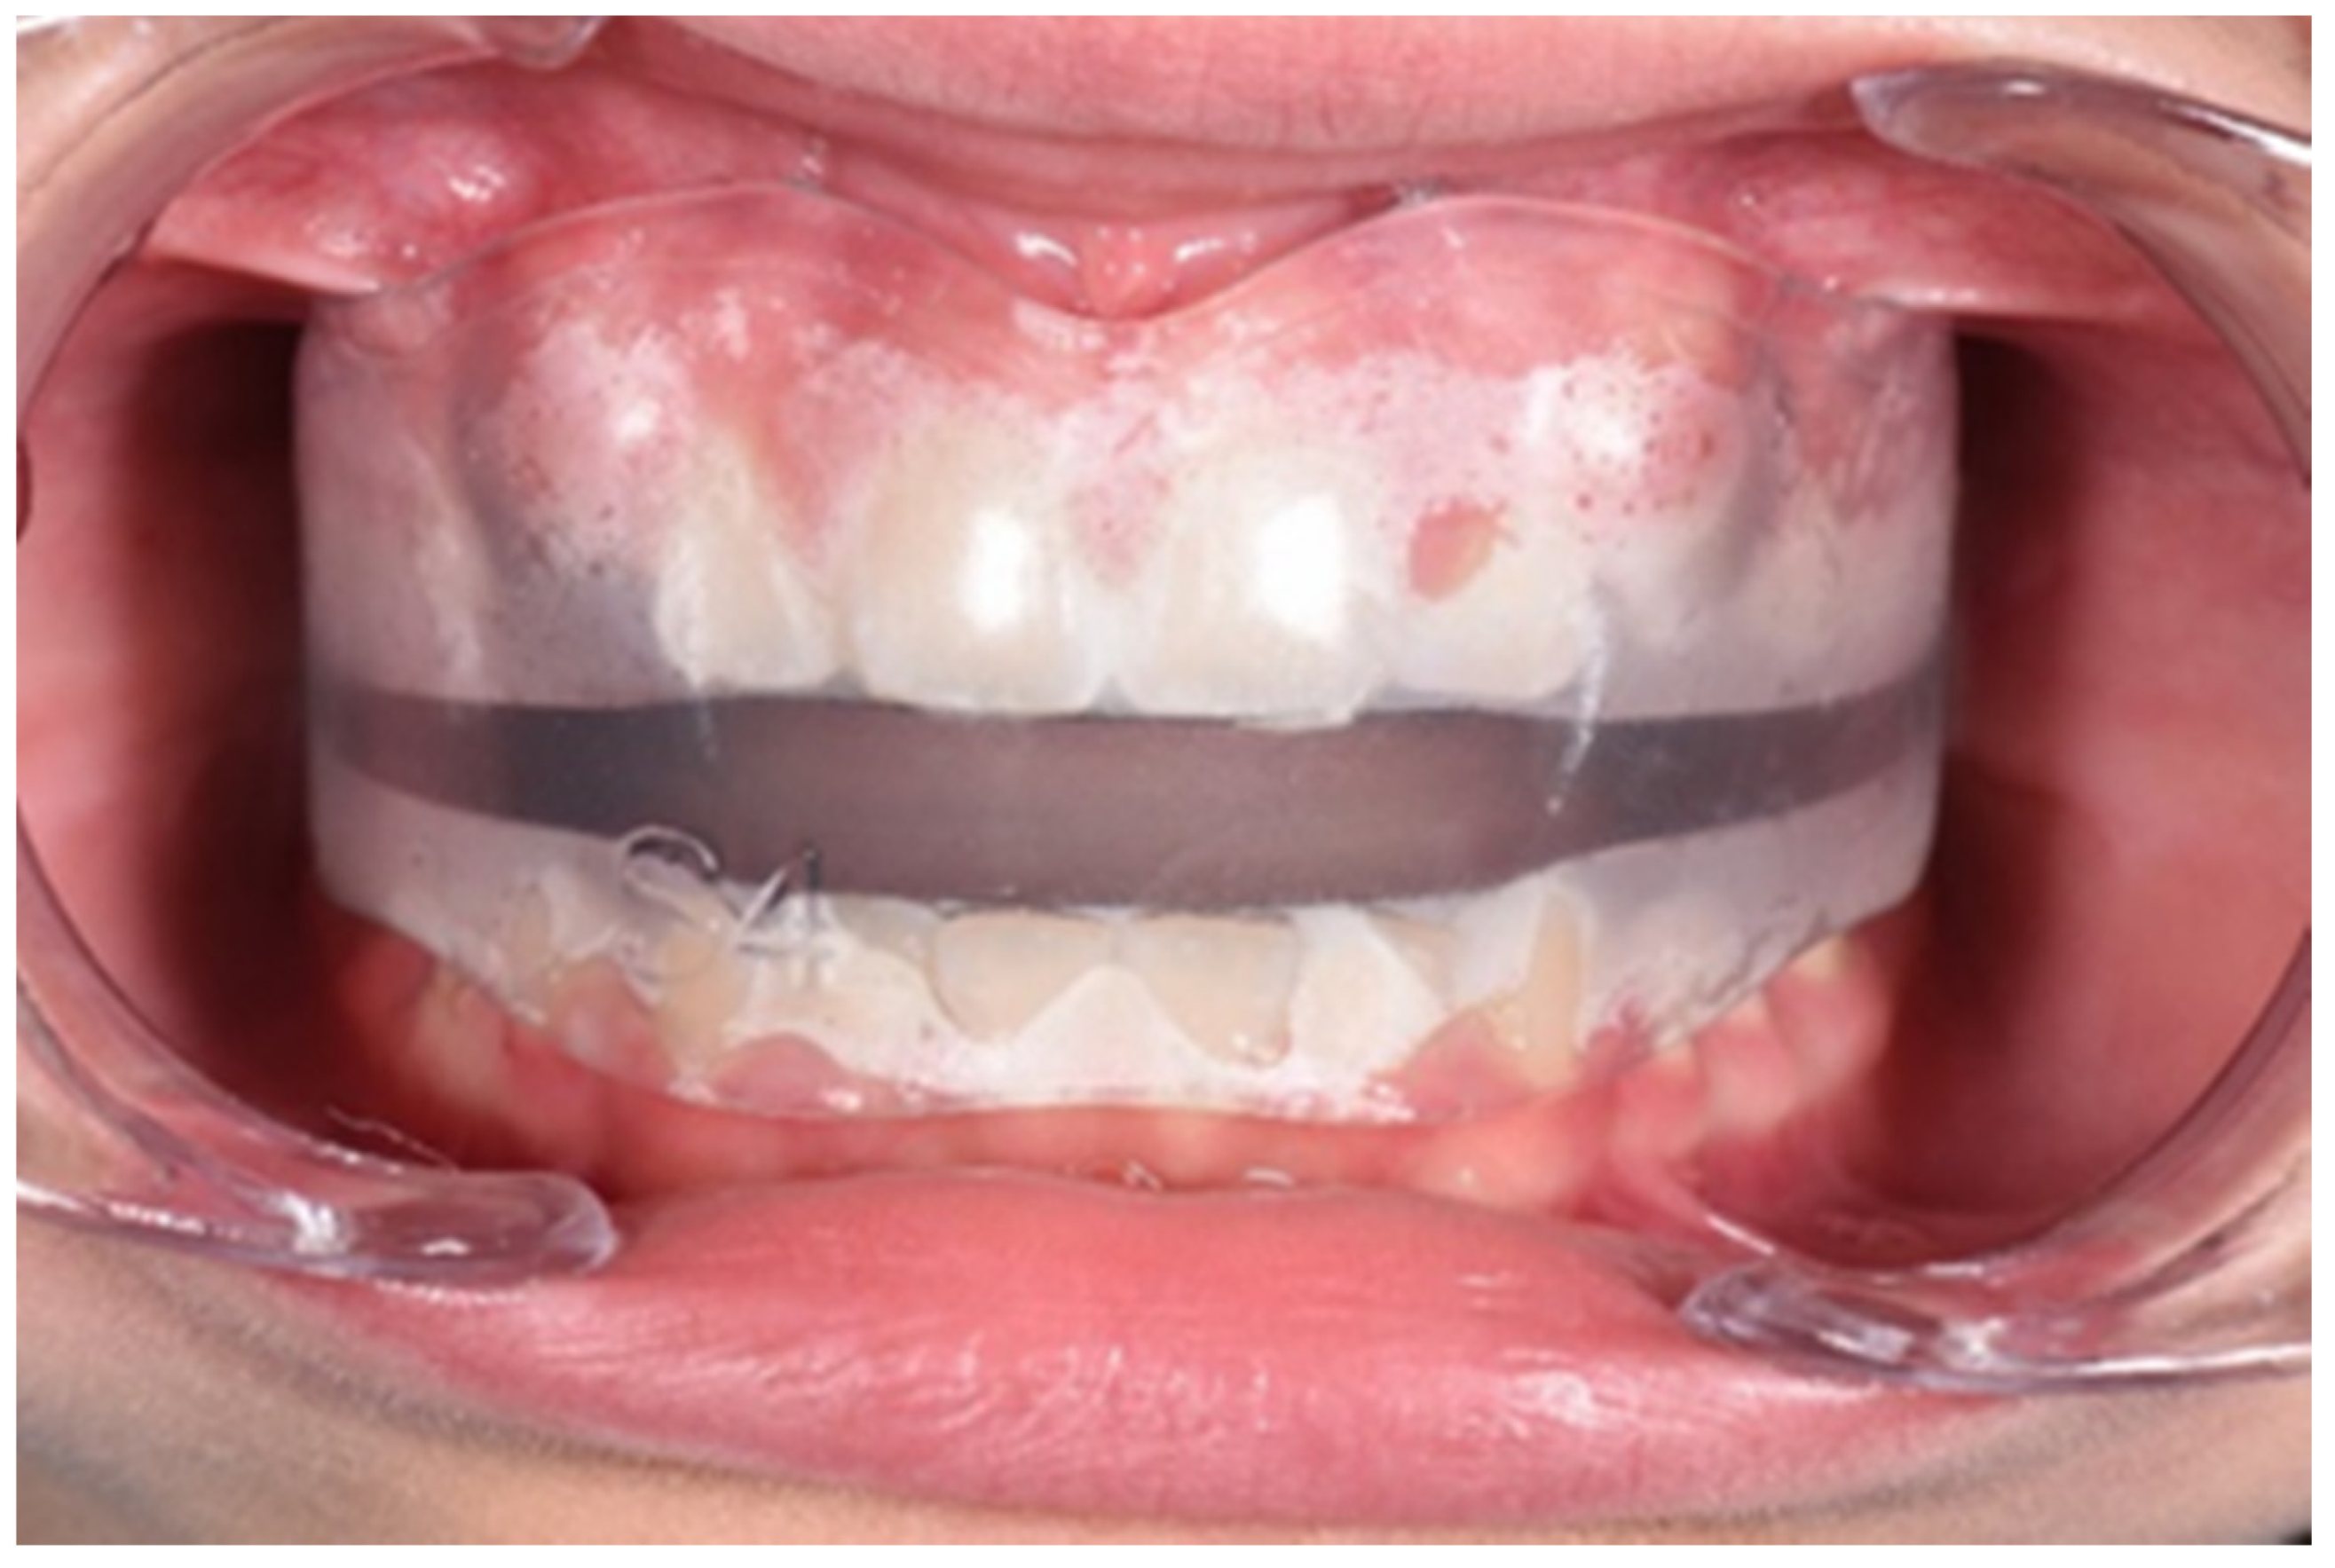

3.1. Clinical Case #1

3.2. Clinical Case #2

3.3. Clinical Case #3

3.4. Clinical Case #4